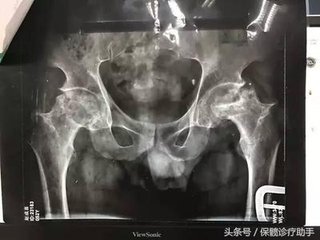

外伤性股骨头坏死的临床症状

一.外伤性股骨头坏死症状

(1)疼痛:外伤经过治疗后,短则三个月,长则1-2年,又出现患髋疼痛,即出现腹股沟及臀后侧间歇性疼痛。活动多时疼痛加重,休息后好转。疼痛时为酸痛不适,或钝痛,或针刺样。随着病情进展,疼痛可转为持续性的,休息时也痛。这种疼痛还放散至膝关节、腰部等,骨质疏松,都是股骨头坏死疼痛的特点。

(2)活动功能障碍,除了典型的髋痛之外,就是活动功能受限与障碍,如大腿外展、内收、伸、屈、内外旋转达等均受限,不能搭腿和盘腿,下蹲也困难等。>>>将自己的症状描述给医生,让医生为您诊断

二.外伤性股骨头坏死体征

(1)步态异常:主要表现为进行性缩短性跛行。跛行的原因是由于髋部疼痛、股骨头变形塌陷、骨盆倾斜,或髋关节出现半脱位所致。股骨头坏死早期可为间歇性跛行,即休息后无跛行,而行走后又出现跛行。到了中晚期后则为持续性跛行了,骨坏死。

(2)肌萎病:当股骨头坏死后发生后,伴随其他症状和体征的出现,肌肉萎缩亦开始发生。即肌肉的容量及张力均渐进下降,主要表现为臀部肌肉、大腿肌肉、小腿肌肉等。

(3)压痛:在肌骨头周围有时显的深压痛,尤其在内收肌止点上有显著压痛,治疗股骨头缺血性坏死。此外,纵向叩击痛、活动痛等亦不同程度存在。

(4)特殊体征:结合病因及发病情况,症状及其他体征,再作些特殊体征检查,而且可以见到阳性体征,如“4”字征(+)、托马斯(Thomas)氏征(+)、艾利斯(Allis)氏征(+)、存德伦保(Trendelenury)氏征(+)等。>>>贵院是怎么治疗骨坏死?